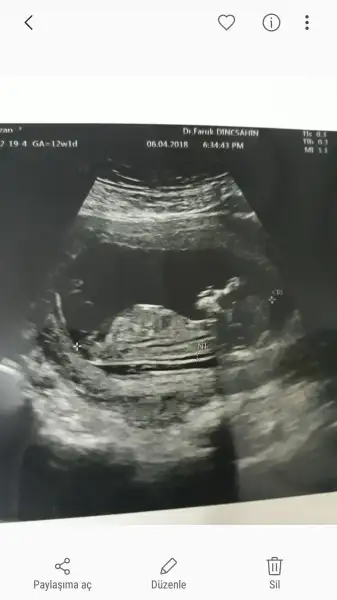

Kız gibi geldi :)Cinsiyet tahmini yaparmisiniz bugun ikili testim vardi cok sukur iyu cikti

Her şeyi güzel olsa bile sırf yaştan dolayı yüksek risk grubuna dahil ediyorlar beni.Allah büyüktür saplıcakla doğsun büyüsün KuzucuklarımızEvet tabi ense kalınlığı 1 mm ise zaten sorun yok demektir. Zaten yüksek olsaydı hastanedeki tanıdığına söylerlerdi.